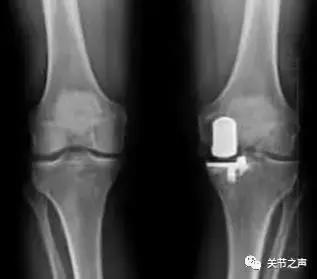

微创单髁表面置换术:主要适用于中到重度关节磨损,但磨损尚且局限于胫股关节的前内侧间室、畸形较轻的病人(一家三口,只是一个人中招),单髁表面置换术手术相对较小,不改变关节的运动学方式,恢复快,效果好。因此,在临床上常见的一侧关节面的磨损往往单间室的微创关节成型手术。然而,这里说的微创并不只是临床手术切口的微小,而是指相对于全膝关节成型术而言。